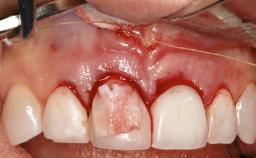

Surgical Treatment of Peri-Implantitis in the Posterior Mandible Associated with Hard- and Soft-Tissue Reconstruction

Paolo Casentini demonstrates that peri-implantitis can be successfully treated even at an advanced stage. He discusses a case in which the existing implants and prostheses were both retained while regenerating the defect and creating a band of keratinized tissue. A 69-year-old female patient was referred by her general dentist for evaluation of a recurrent infection at previously placed and restored implants in the posterior left mandible. The patient’s chief complaint was recurrent swelling and pain in the molar region of the left posterior mandible with discomfort during brushing in the same area. The patient reported receiving two implants (36 and 37) nine years earlier.